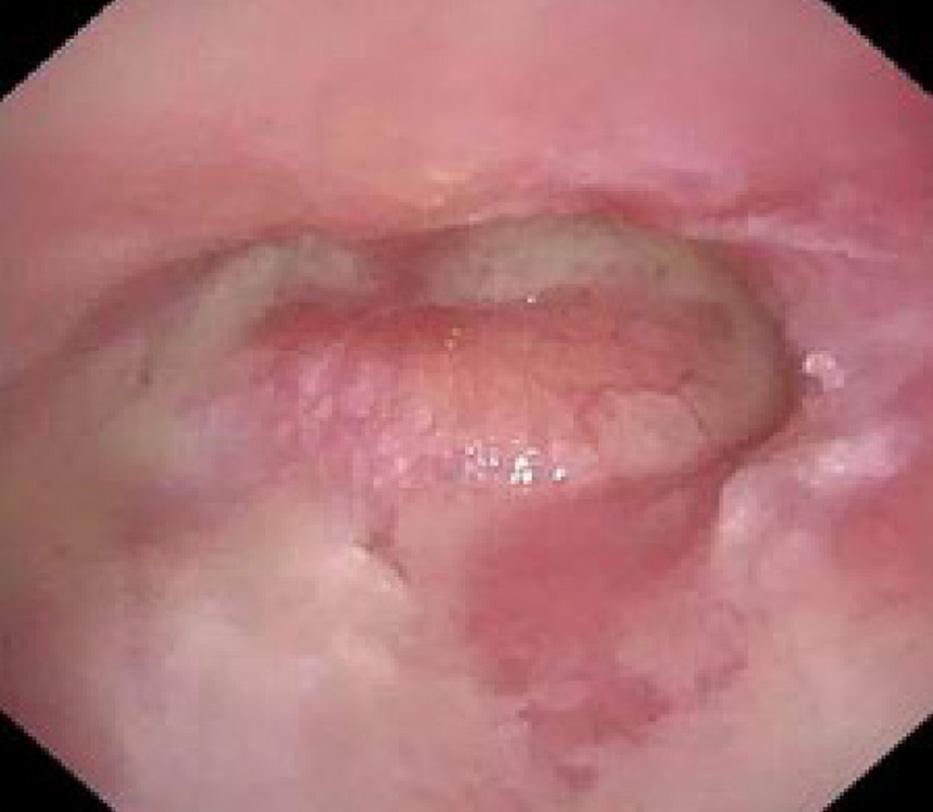

295 Bezold Abscess in a Case of Eosinophilic Otitis Media

Satoshi Tsuruta, Takashi Fujiwara